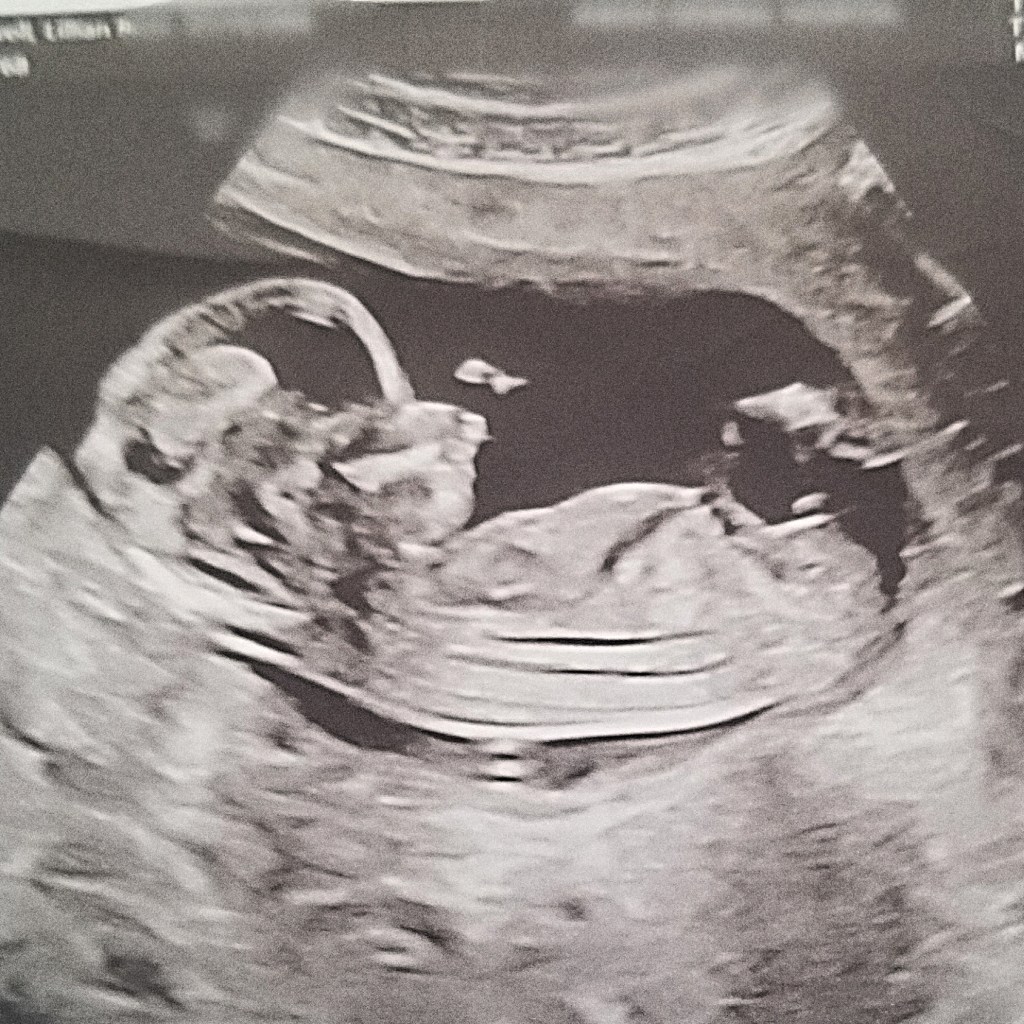

I was completely heartbroken by the fact that I wouldn’t getting any prenatal care because if anything went wrong with me or my baby, who would know? During this time, I still did manage to go for regularly scheduled blood tests and ultrasounds, but other than that, I honestly was praying that God would give me peace of mind because it is so easy for fear and anxiety to set in. Is my baby ok? Why don’t I feel baby moving? What if baby’s in distress? I had so many concerns and was on the verge of buying a baby doppler so that I could at least check the baby’s heart rate myself and know that they’re still alive! My amazing neighbour who also happens to be an RN, so happened to have a baby doppler which saved me some $$$ and saved my sanity! Baby was great!

Shortly before my second trimester ended, my husband was temporarily laid off, along with millions of people around the globe due to the corona virus. We weren’t concerned about the lay off situation because we knew God would take care of our family during the madness and he totally did. We didn’t stress about making ends meet or hated the thought of being “trapped” at home with our family as so many people have expressed. We soaked up all the time together with joy and whenever hubby or I needed a break from our wild bunch of kiddos, we would take turns going out for a drive here and there. PLUS, I have to admit, I was glad that my husband was home for the last few months to help with the kids while I felt like was dying from this pregnancy! He was and still is such a huge help to me and I don’t know how I would have managed without him being home. Temporary lay off was certainly a blessing in disguise. The second trimester wasn’t all cupcakes and fairy tales but it was WAY better than the first. I felt a relief in my body, I had a higher level of energy and as things started to ease up with covid-19, my doctor called me to resume my prenatal care which I was so happy about! Oh, and we found out we are having another BOY!!! I have aches and pains, feel exhausted all the time but still was so glad with how my second trimester went overall.

Other than that, unfortunately i’ve temporarily been put on bed rest due to the fact that i’m having intense braxton hicks contractions and they’re coming quite frequently. I am scheduled to go for an ultrasound very soon in order to check on my cervix which will confirm if I’m at risk for preterm labor or not. If everything is okay, then I can be taken off bed rest and resume my daily activities with the little bit of energy that I have. Or alternatively, I will need to stay on bed rest for the remainder of the pregnancy to make sure baby boy stays put for as long as possible!